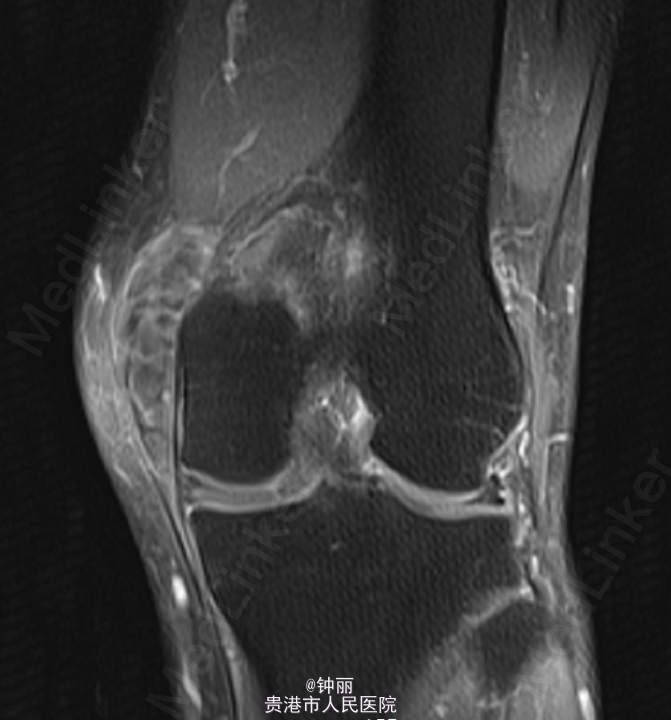

患者左膝内侧可及约8*5cm左右肿块,肿块质韧,无压痛,边界尚清。关节活动无受限,浅表静脉无怒张,末梢足趾下下肢感觉、活动可,余肢体无殊,病理征阴性。左膝关节增强MR:左膝部(股骨下端内侧髁内后方)混杂信号占位,考虑滑膜肉瘤可能,左膝内侧半月板后角撕裂,左膝关节囊少量积液。